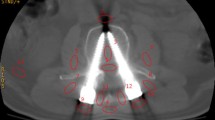

Visual comparison of resulting image quality using Local-MAA interactive optimization with defined task on thoracic vertebra TH11, global trajectory scores (Global-MAA) and without any MAA system (No-MAA). The six pedicle screws in vertebrae TH9–TH11 are depicted alongside the guidance overlay and trajectory score map used to decide for a C-Arm tilt

In addition to these quantitative findings, Fig. 4 illustrates an example. The scene includes six pedicle screws and towers in vertebra TH9 through TH11 of the thoracic spine. As an imaging task, the pedicle screws in vertebra TH11 are selected from procedural context. The guidance image produced by the proposed Local-MAA method for the selected tilt of positive 24.5\(^\circ \) shows the screws in TH11 (top) in blue color. The trajectory scores from the globally averaged MAA method on the other hand suggest to tilt into negative direction. Comparing the depicted pedicle screws, it is obvious that both tilted acquisitions drastically improve image quality compared to the bottom row featuring the reference scan. However, looking at the right two columns, we observe that the scan acquired with Local-MAA optimizes for the screws in TH11, whereas the global MAA optimizes for global image quality including the towers or other obstacles, which are not relevant in this use case.